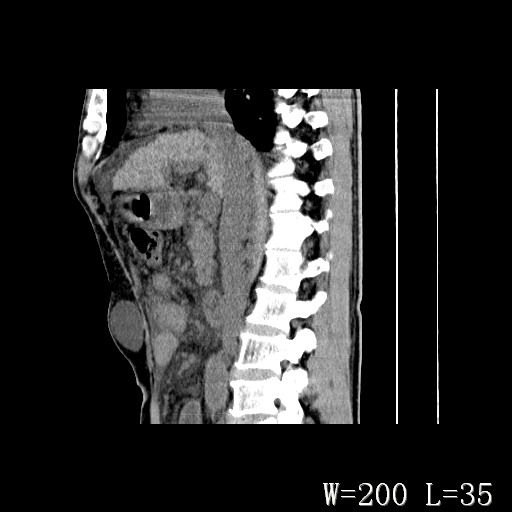

标题: CT27080:腹壁肿物?

男,52岁,门脉高压断流术后1年,发现腹部肿物2月。

1)前腹壁中线区(脐上方)囊性占位性病变,考虑淋巴囊肿。2)腹水。